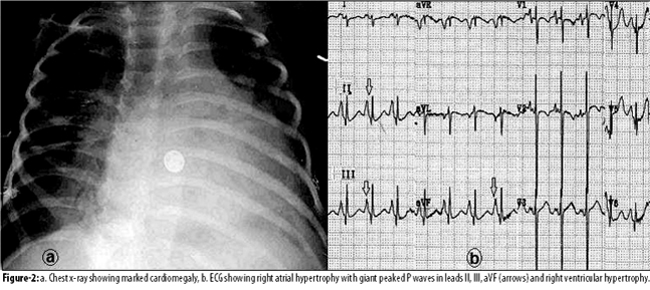

On examination, reduced height and body mass index (BMI), alopecia, prominent forehead, protuberant eyes, flattened nose bridge, deformed hypodentition, deformed mandible, and dry sclerodermic purpuric skin patches over the abdomen and limbs were observed. The hands and feet were small with malformed rigid fingers and toes. Hearing was within normal limits, but the boy was unable to speak. Pulse was 144 beats per minute and the blood pressure was 90/70 mmHg. Crepitations in the lung fields and a proto-diastolic gallop were audible. A short systolic (sclerotic) murmur was audible over the mitral and the aortic areas and signs of congestive cardiac failure were present. On laboratory investigations, haemoglobin was found to be 9.3 G/dl, urea was 47mg/dl, and serum cholesterol was 187mg/dl. Chest x-rays showed cardiac enlargement, and the electrocardiogram (ECG) showed right atrial hypertrophy with giant peaked P waves (leads II, III and aVF) and right ventricular hypertrophy (Figure-2).

We are reporting herein a 6-year-old boy with progeria, who presented with respiratory infection and cardiac failure and was confirmed to have cardiovascular atherosclerotic changes, which included a characteristic systolic (sclerotic) murmur of valvular sclerosis, and signs of congestive cardiac failure. Chest X-rays showed cardiomegaly and the electrocardiogram showed right atrial and ventricular hypertrophy. Echocardiography confirmed dilated atherosclerotic aortic root with septal involvement, and thickened sclerotic aortic, mitral and tricuspid valves, with atrial dilatation and systolic and diastolic ventricular dysfunctions.